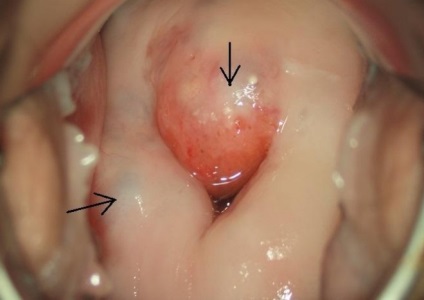

Nagy gennyes daganat

Kép külleme ciszták a méhnyak, azt mutatja, kóros előre. Ilyen nagy genny képződése befolyásolja legtöbb nyálkahártyák és okozhat betegséget és a kísérő betegségek.